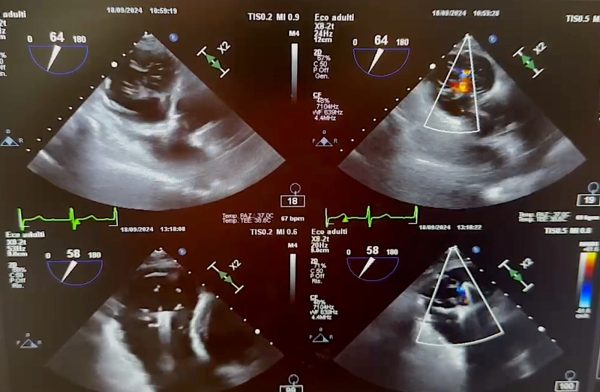

L’emodinamica del presidio ospedaliero “San Giovanni di Dio” di Agrigento ha eseguito il primo intervento di riparazione della valvola tricuspide tramite cateteri endovascolari, senza ricorrere alla cardiochirurgia tradizionale, su un complesso paziente ultraottantenne affetto da grave insufficienza valvolare e scompenso cardiaco. Si tratta di una delicata operazione di riparazione della valvola che separa le camere cardiache destre praticato in pochi centri in Italia. La procedura è stata condotta in anestesia generale utilizzando le immagini ecografiche “bi e tridimensionali” trasmesse da una sonda transesofagea incrociate con immagini radiografiche multiplanari, ad alta risoluzione, che hanno permesso di posizionare due clip sui lembi della valvola ottenendone la stabilizzazione e l’efficace riparazione. La tecnologia è simile a quella già utilizzata dagli stessi professionisti del San Giovanni di Dio ma per la riparazione della valvola mitralica.